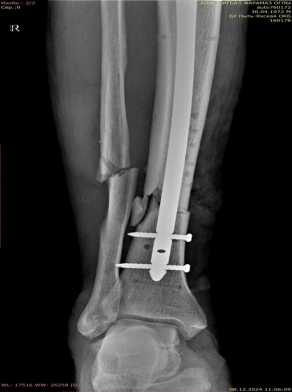

После заживления раневого процесса и спадения отека на 12-е сутки выполнен закрытый блокируемый остеосинтез интрамедуллярным стержнем Expert внеочагово (рис. 6).

Рис. 6.